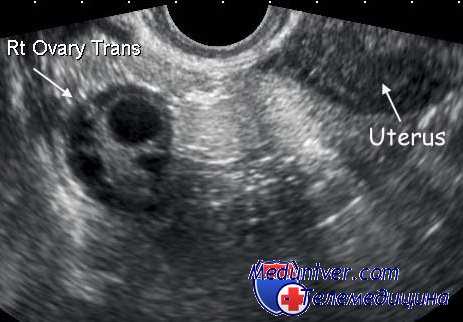

Диагностика липоидоклеточных опухолей. Диагноз маскулинизирующей опухоли яичника ставится на основании появления симптомов вирилизации и обнаружения опухоли яичника, обычно подвижной, плотной консистенции, сохраняющей его форму. При гормональном исследовании часто отмечается увеличение экскреции 17-КС мочи при нормальном количестве ДЭА. Фракционное определение 17-КС мочи указывает на повышение андростерона и этиохоланолона. В то же время 17-КС мочи при маскулинизирующих опухолях яичника могут оставаться в пределах нормы. Проба с дексаметазоном не вызывает снижения их уровня. Исключением в этом отношении является адреналоподобная опухоль.

Иногда для уточнения диагноза используют лапароскопию или гинекографию, которые позволяют обнаружить опухоли яичника небольших размеров. Иногда диагноз маскулинизирующей опухоли яичника при наличии вирильного синдрома ставится на основании исключения других причин вирилизации из-за незначительных размеров. Согласно данным литературы, 1/3 маскулинизирующих опухолей при влагалищном исследовании не пальпируется.

Нужно также иметь в виду, что маскулинизирующие опухоли яичника типа арренобластомы обычно встречаются у женщин детородного возраста [Jakobovits], появление же симптомов вирилизации в период менопаузы заставляет предположить наличие крайне редко встречающейся липоидоклеточной опухоли яичников.